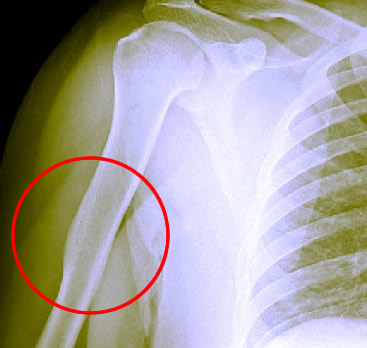

You occasionally hear that bones are stronger where they have been fractured and healed. This Healed Humerus Bone

A Healed Humerus Bone. Other Than the Slight

Deformity,The Bone Looks Fairly Uniform

goes back to the golden age of the pirates (and before.) Writing in the late 16th century, Ambroise Paré said that the healed fracture callus "is so hardened in time, that the bone thereafter in the broken part is seene to be more firme and hard than it is in any other"1. Writing in the late 17th century, Richard Wiseman cites Hippocrates, noting that "though it [the callus] be not Bone, it is so hard, saith he, that if the Member hap again to be broke, potiús in alia parte frangitur, quám ubi Callus est genitus, it breaks any where rather than in the Callus."2

In fact, they had it wrong. While the healed site may temporarily become stronger as the new callus is built up while the surrounding bone loses a little strength because the limb isn't being used, over the long haul it isn't stronger. Dr. Terry D. Amaral, director of pediatric orthopedic surgery at Montefiore Medical Center in the Bronx notes that "in studies in which healed bones were subjected to bending and twisting forces, the repaired bones were capable of breaking anywhere, including the fracture site."3